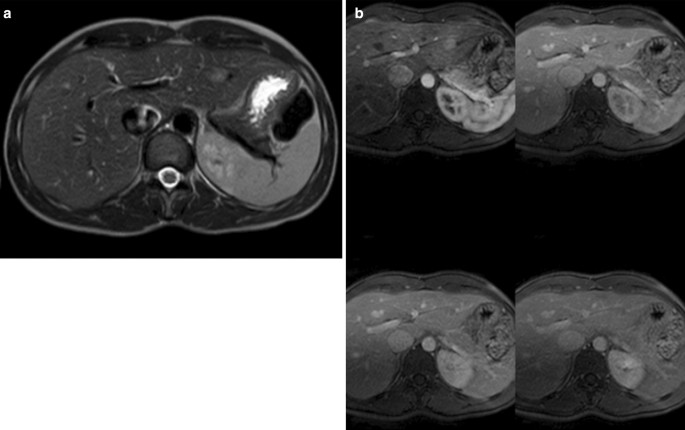

A slowly growing focal lesion in hepatic segment 6 was observed on abdominal ultrasound during follow-up (Fig. 4). In June 2019 an MRI was performed to characterize the lesion which had 3 × 2.2 cm of size. It was hypointense in T1 and discreetly hyperintense in T2, with diffusion restriction. In the dynamic study, it presented an enhancement in the arterial phase with washing in the rest of the phases, with a more hypovascular area at the back. The lesion was indeterminate by image, but its hypervascularity could be oriented to a hepatocellular origin (Fig. 5). Metastasis was not detected on a preoperative CT scan.

a, b MRI scans with intravenous contrast. Focal liver injury at segment 6 of 3 × 2.2 cm, hypointense at T1, and discrete hyperintense at T2 with diffusion restriction (a). In the dynamic study, it presented enhancement in the arterial phase with washing in the rest of the phases, with a more hypovascular area afterwards (b)